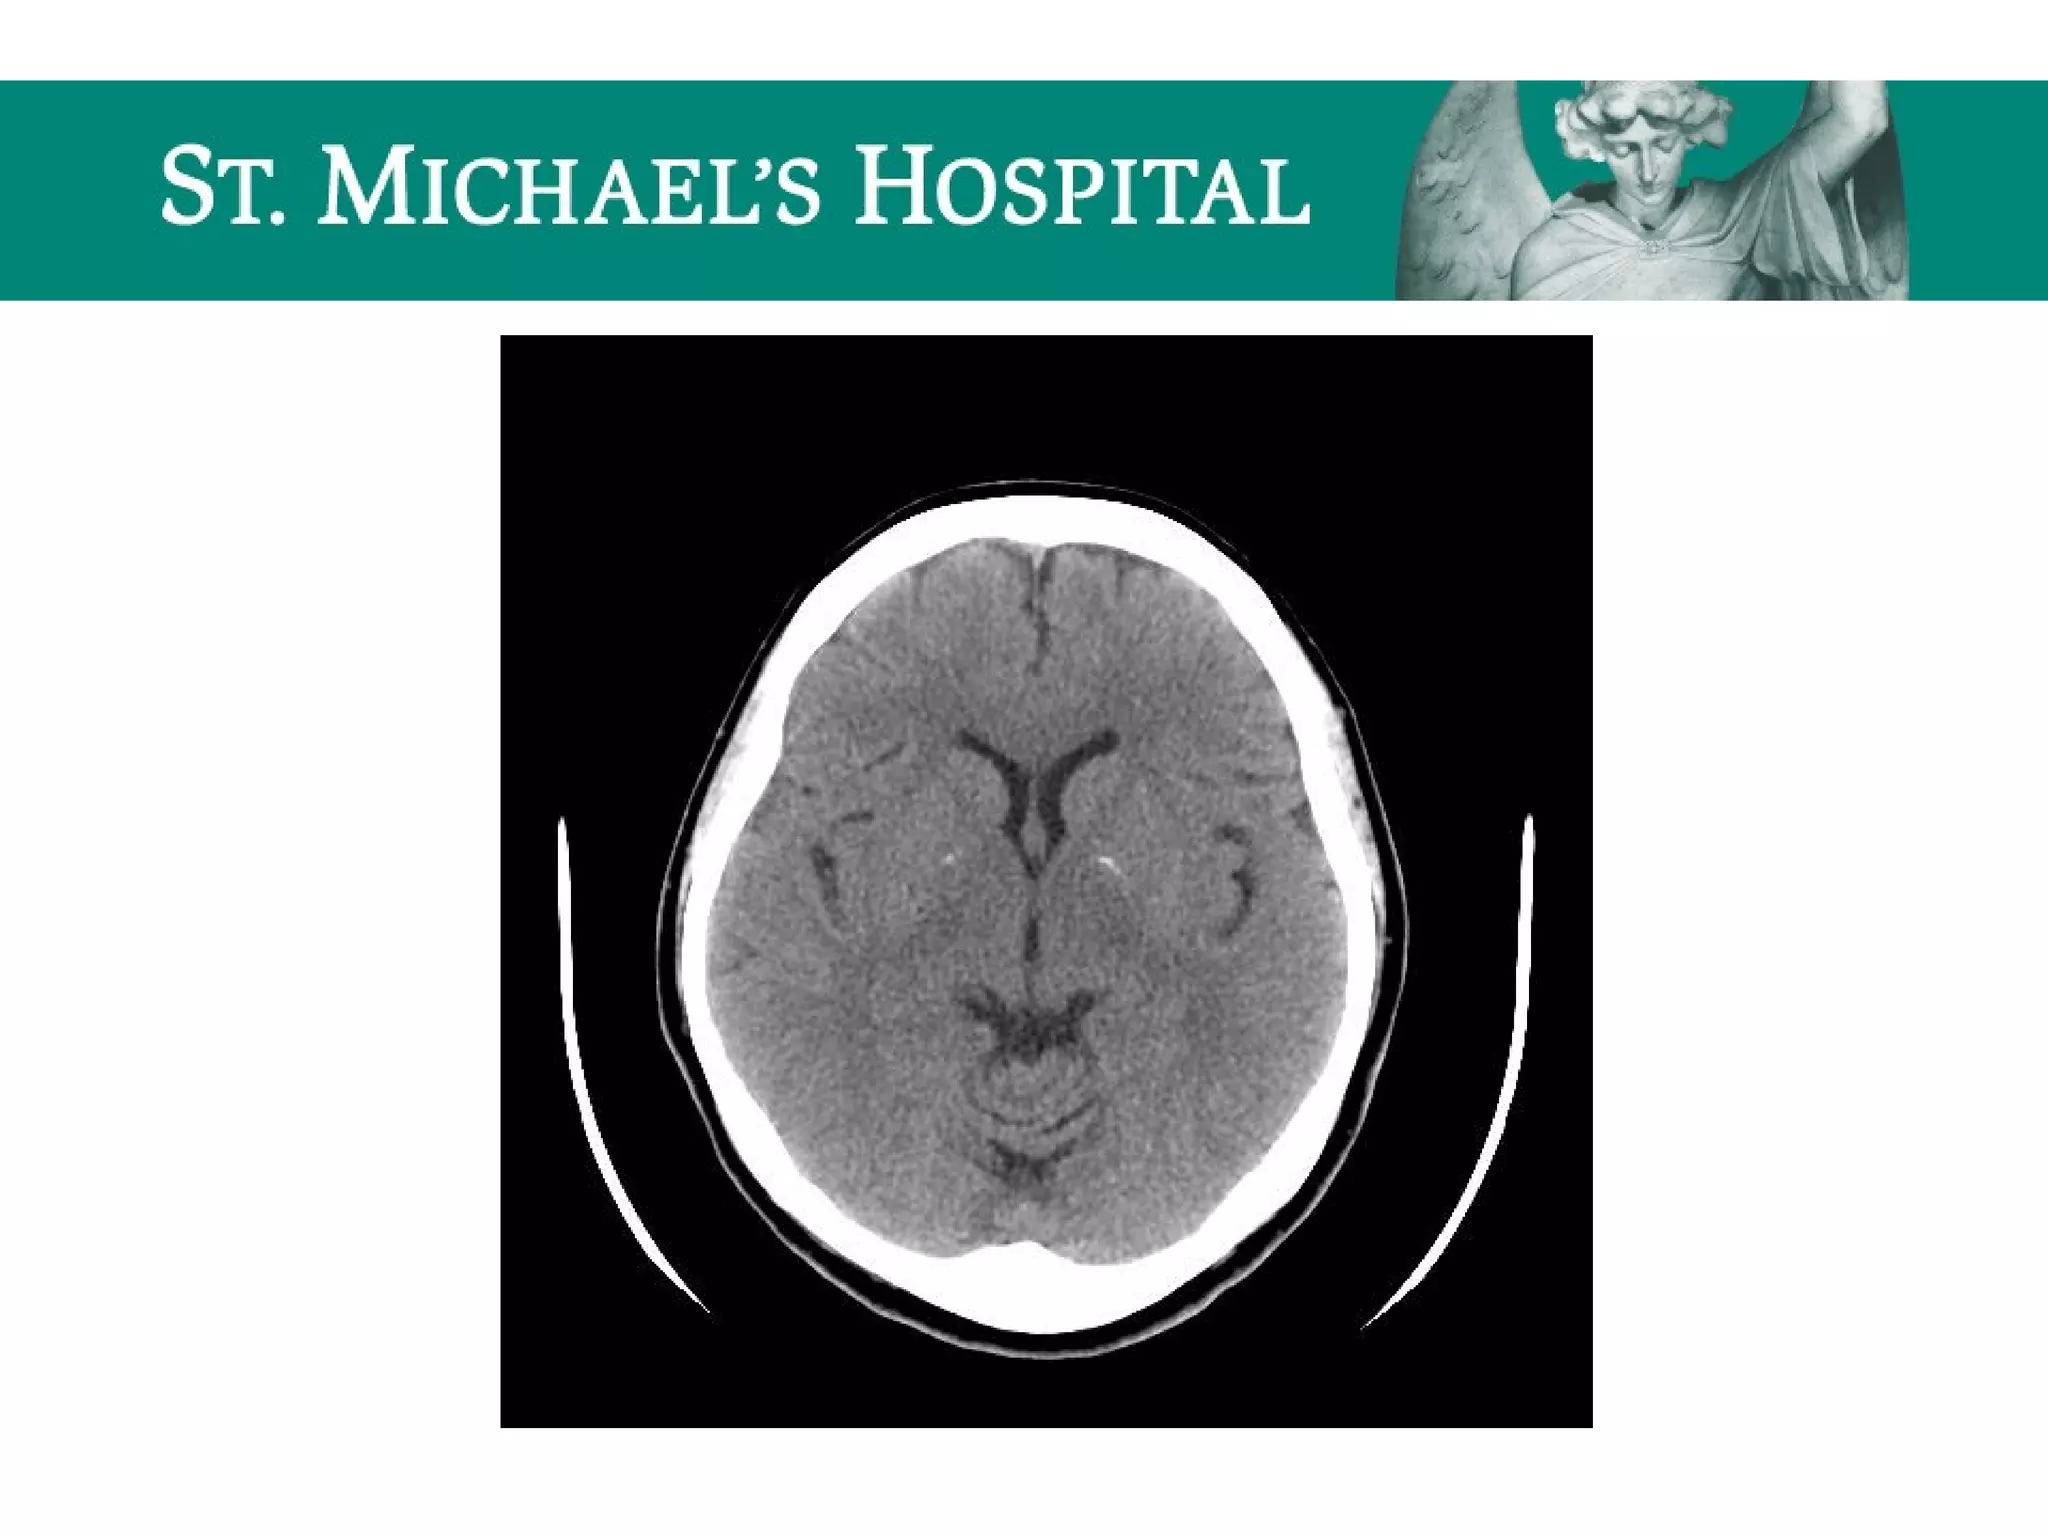

Acute Ischemic Stroke

 Unenhanced CT has low sensitivity – primarily done to rule out

hemorrhage/other causes of patient’s symptoms

 Hyperdense MCA = acute intraluminal thrombus (corresponding loss of

contrast opacification on CTA); seen in 25-50% of acute MCA occlusions.

 Loss of gray-white differentiation:

 insular ribbon sign

 basal ganglia sign

 Sulcal effacement (secondary to cytotoxic edema)

Acute Ischemic Stroke Unenhanced CT has low sensitivity – primarily done to rule out hemorrhage/other causes of patient’s symptoms  Hyperdense MCA = acute intraluminal thrombus (corresponding loss of contrast opacification on CTA); seen in 25-50% of acute MCA occlusions.  Loss of gray-white differentiation:  insular ribbon sign  basal ganglia sign  Sulcal effacement (secondary to cytotoxic edema)